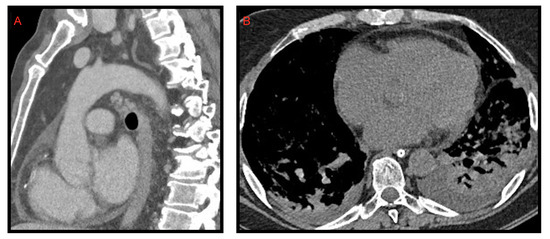

Pericardial effusion can be defined as the presence of more than 50 mL of liquid between the pericardial sheets. As already mentioned for the pleural effusion it is not characteristic of the COVID-19 thoracic involvement. In fact, it was observed by Li et al. [8] in 4.8% of cases. However, in this study, it is also described as a manifestation associated with the most compromised patients (Figure 4).

Ali Sabri et al. [13] found a 7.9% frequency of pericardial effusion. Furthermore, from their analysis, it emerged that pericardial effusion could be considered an important factor for admission to intensive care unit (ICU), as it could be an indicator of myocarditis or cardiomyopathy caused by COVID-19, but they did not confirm this hypothesis with echocardiography.

Grassi et al. [9] describe pericardial effusion in 16.7% of patients, proposing a relation with heart damage; Shi et al. [14] associated it with a higher risk of in-hospital mortality.

Figure 4. Pericardial effusion on CT, sagittal (A) and axial (B) images, in two patients admitted to intensive care unit. In image B, bilateral pleural effusion is also noted.